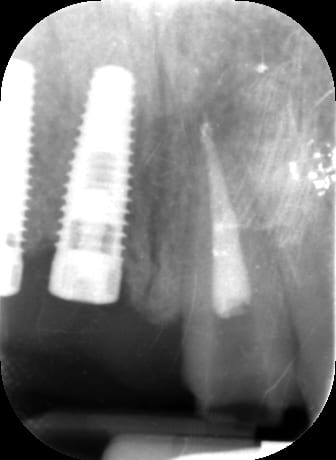

Bon voila le scann de 11-12 (pas 21-22 comme noté)

C'est vrai que j'ai à mort d'os en épaisseur.

Le manque est surtout en hauteur.

Dans tous les cas je refais 21 en même temps.

j'ai l'impression qu'il ne manque pas d'os en verticale, ou à peine en 12.

Un bon cj avec un lambeau décalé en palatin ou en rouleau pour gagner en épaisseur me semblerai suffisant

le montage guide RX laisse supposer un manque d'un mm en 12 et ok en 11. Surcomble en cj pour en éliminer au cas où avant les empreintes